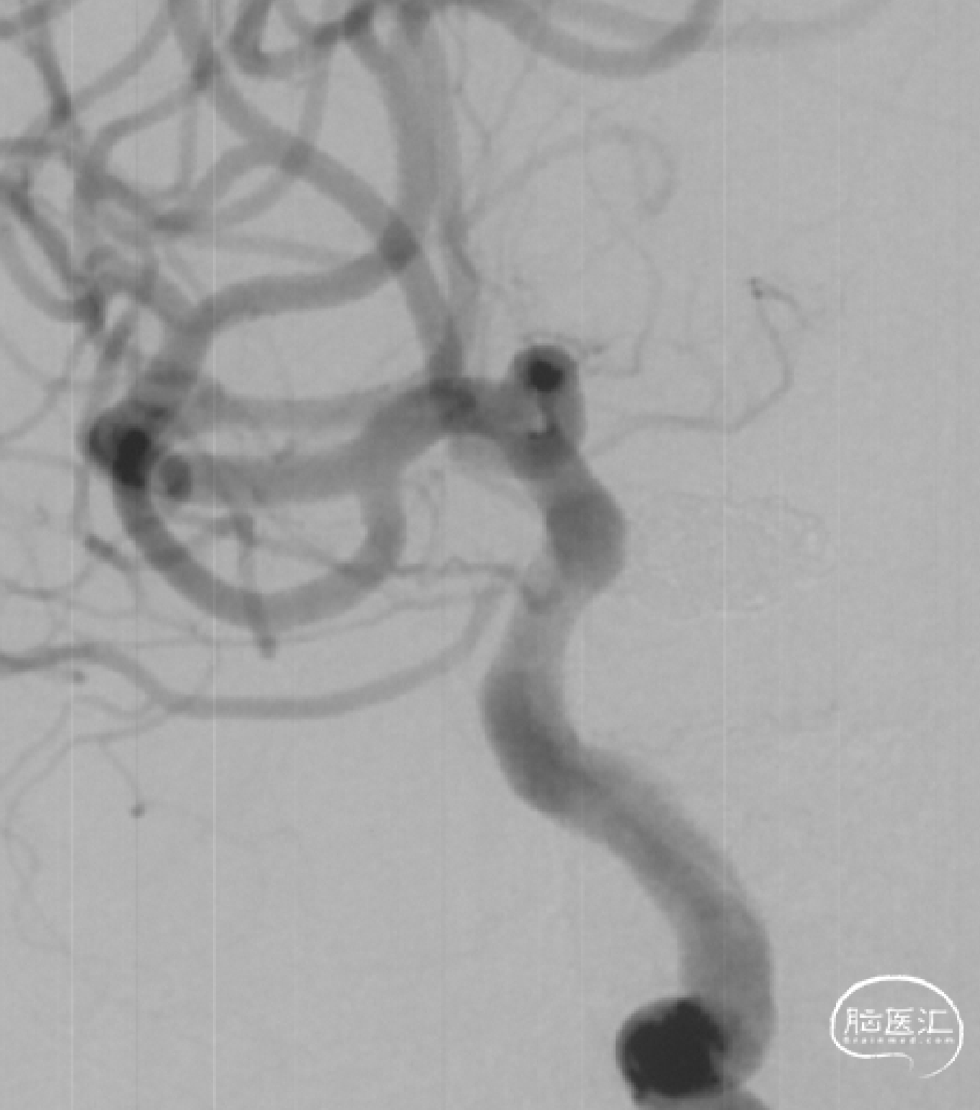

载瘤动脉近端直径4.24mm,远端直径3.05mm,选择通桥麒麟™血流导向密网支架 TQL-40-45。

微导丝囊内成绊,超选到大脑中动脉M1远端。

撤出微导丝,送入弹簧圈微导管至瘤腔内。

固定输送系统,回撤微导管,逐步释放通桥麒麟™血流导向密网支架头端,至头端张开为V型。

继续送入弹簧圈填塞。

再次造影确认打开情况,用微导丝继续按摩支架尾端。